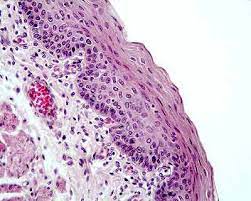

- Tinción con hematoxilina y eosina: Una vez que las secciones de tejido están montadas en los portaobjetos, se procede a la tinción con H&E. La hematoxilina tiñe los núcleos celulares de color azul oscuro, mientras que la eosina tiñe el citoplasma y otros componentes celulares de color rosa a rojo. Esta tinción diferencial resalta las diferencias en la morfología y la composición celular de los tejidos.

- Microscopía óptica: Finalmente, las muestras teñidas se examinan bajo un microscopio óptico. La coloración con H&E permite a los patólogos y los investigadores observar y analizar la estructura y la organización de las células y los tejidos. Esto es fundamental para el diagnóstico de enfermedades, la investigación científica y la comprensión de la anatomía normal y patológica.